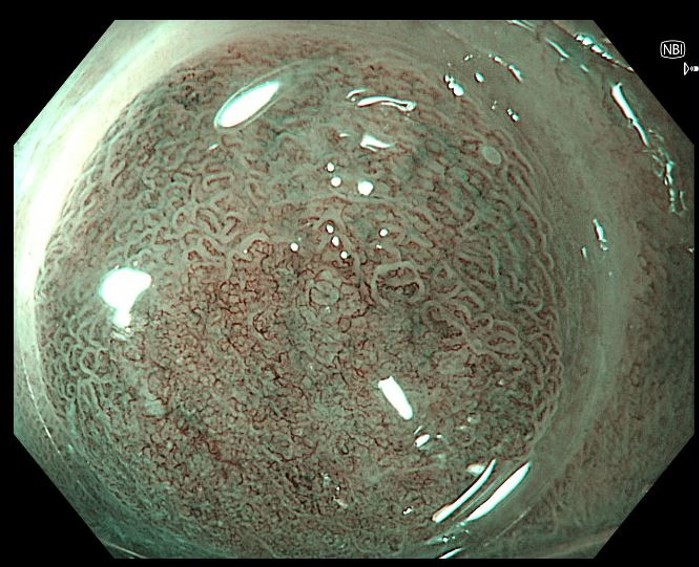

2. Demarcation line of neoplastic lesion nicely visualized with narrow-band imaging and near focus and distal attachment cap

Inspection with narrow-band imaging (NBI), near focus and a distal attachment cap helps in delineating the neoplastic lesion. Inspection clearly shows a sharp demarcation line between normal versus irregular mucosal and vascular pattern.

Inspection with NBI, near focus and the use of a distal attachment cap to stabilize the mucosa, helps to identify the delineation line of the neoplastic lesion by clearly showing the border between normal mucosa and irregular mucosa and irregular vascularity.